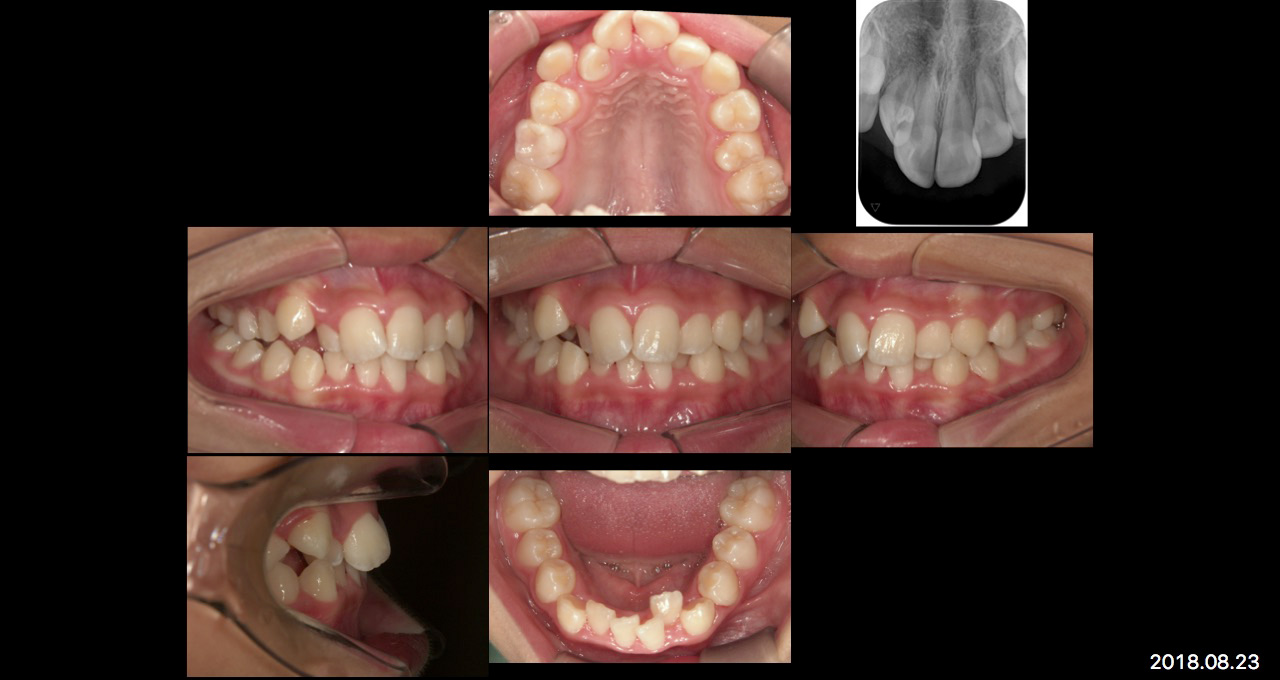

小学生になると乳歯から永久歯に生え変わりが始まります。前歯が生え変わっていくときに、きれいに並ばなくてガタガタになってしまったり、明らかに永久歯が生えるスペースが足りなかったりする子どもたちが増えています。

成長の状態によっていくつかの治療方法があります。成長期の子どもの歯並びが気になる、鼻が詰まっている、口が開いていることが多いなど、子どもさんの状態で気になることがあればお気軽にご相談ください。